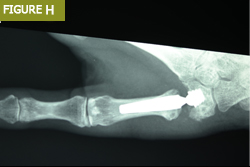

Parmak eklemi değiştirme, özellikle parmak eklemlerinde ciddi ağrı ve hareket kısıtlılığı yaşayan hastalar için uygulanan bir cerrahi yöntemdir. Bu işlem, romatoid artrit, osteoartrit veya travma sonrası eklem hasarı olan kişilerde sıklıkla tercih edilir.

Parmak eklemi değiştirme işlemi, hasarlı eklem yüzeylerinin çıkarılarak yerine protezlerin yerleştirilmesiyle gerçekleştirilir.

Bu işlem, özellikle başparmak ve diğer parmak eklemlerinde uygulanır ve hastaların günlük aktivitelerini daha rahat yapmalarını sağlar.

El ve parmak eklem protezi kullanılarak yapılan bu işlem, hastaların yaşam kalitesini önemli ölçüde artırır. Ancak, her hasta için uygun olmayabilir. Cerrahi öncesi detaylı bir değerlendirme yapılması gerekir.

Parmak eklemi implantları için kullanılan malzemeler silikondan çeşitli sentetik plastik ve metal alaşımlarına kadar değişebilir (Şekil C). Kullanılan malzeme ve implant, ilgili eklem, hasta gereksinimleri ve mevcut cerrahi uzmanlık gibi çeşitli faktörlerle birlikte altta yatan patolojiye bağlıdır.